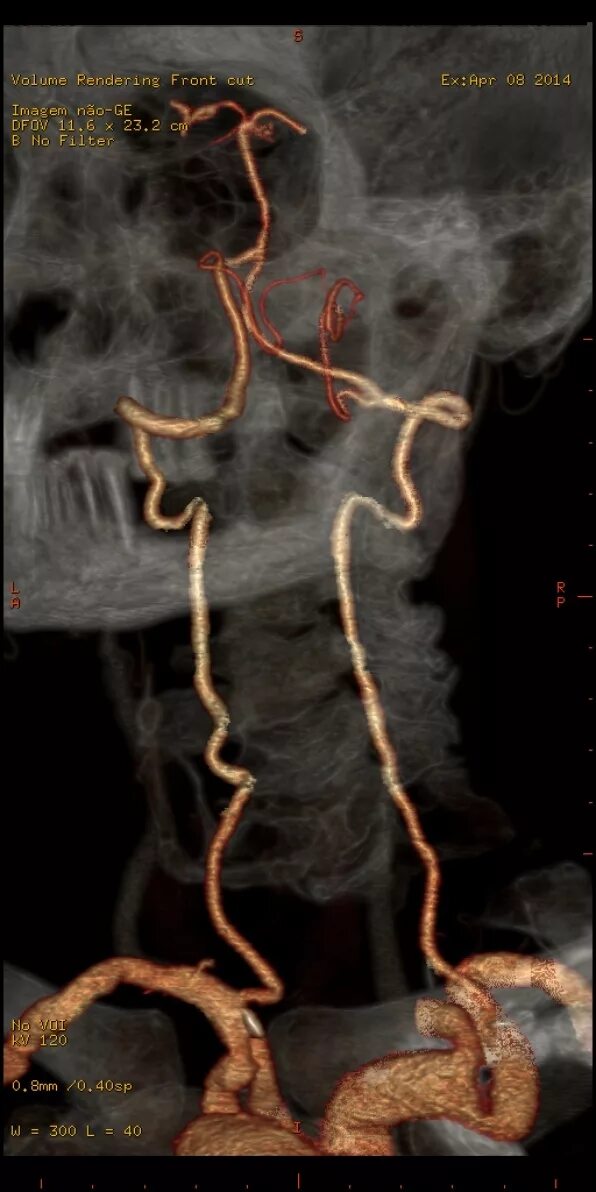

Гипоплазия интракраниального сегмента